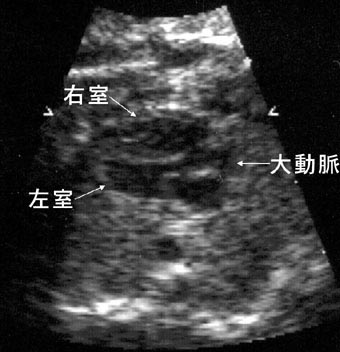

ファロー四徴

心室から大血管の長軸断面で、大動脈は左室と右室の間の心室中隔に騎乗している。